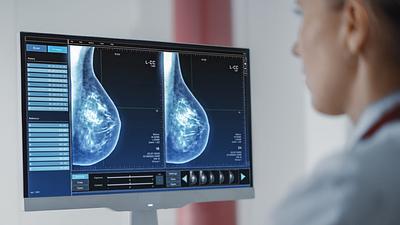

IA antecipa risco de câncer de mama por até cinco anos

Modelo de inteligência artificial analisa mamografias para avaliar risco do desenvolvimento da doença. Técnica pode ajudar a identificar casos não detectados pelo exame tradicional.

Pesquisa em larga escala aplica IA para detectar câncer de mama

A ferramenta de IA foi aplicada em tempo real e envolvendo um grupo ampliado de pessoas, em vez de ser utilizada posteriormente como vinha sendo feito até agora.